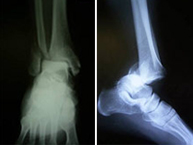

La articulación del tobillo une la pierna con el pie y su funcionamiento permitela normal deambulación que realizamos. Están implicados los tercios inferiores de la tibia y el peroné que articulan con el astrágalo del pie. Es una región anatómica muy susceptible de recibir lesiones fundamentalmente de dos tipos: alta energía en accidentes laborales o de tráfico produciendo las temibles fracturas de pilón tibial o de baja energía en el ámbito deportivo por mecanismos de torsión produciendo las fracturas maleolares.Las fracturas de pilón tibial se acompañan de gran afectación de los tejidos circundantes al hueso por lo que requieren un tratamiento muy meticuloso de estos tejidos antes de resolver la lesión ósea. En las fracturas maleolares, características de deportes de salto y giro como fútbol, baloncesto, monopatín, voleibol, artes marciales, etc., la lesión se produce a nivel del mecanismo de pinza conocido como mortaja tibioastragalina que impide en condiciones normales que el pie se separe de la pierna.

Las lesiones del tobillo, como en general de todas las articulaciones del esqueleto, requiere una reconstrucción anatómica para evitar la rigidez articular por lo que se realizará una cirugía rápida y mínimamente invasiva para reincorporar al paciente lo antes posible a su actividad previa.